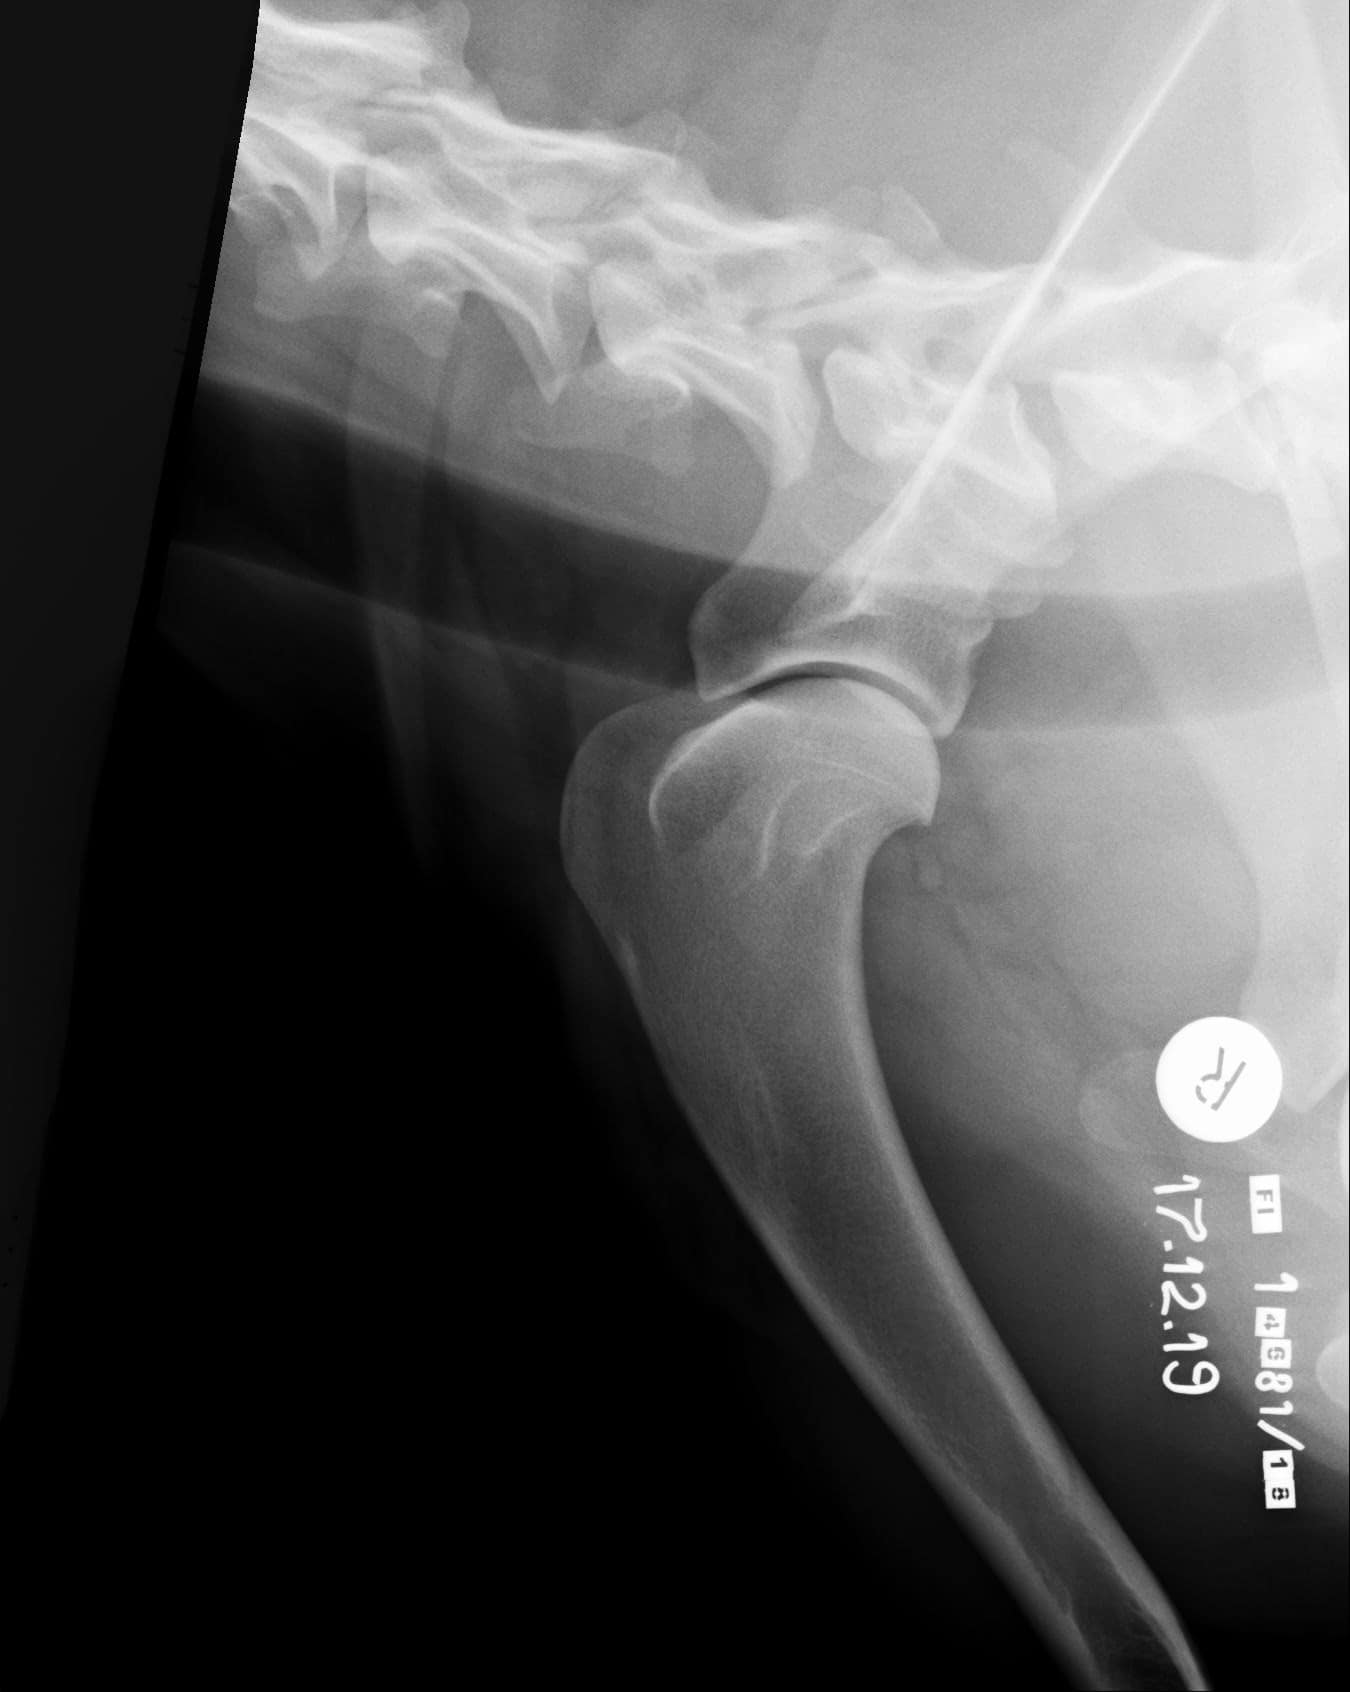

Tähän mennessä Iivo on ollut täysin terve ja Iivo tutkittiin luustoltaan terveeksi joulukuussa 2019. Luonnekuvaukseen (MH, laukausvarma) Iivo osallistui elokuussa 2020.

| Lonkat: | A/A |

| Olat: | Ei todettu/ Ei todettu |